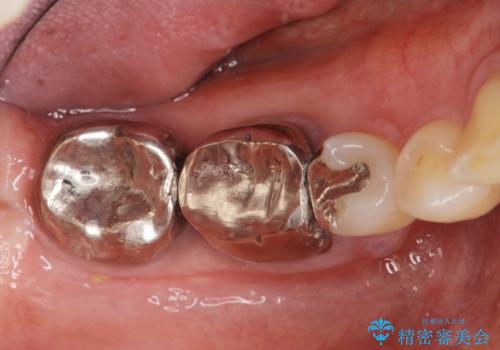

- 他院で根管治療を受け銀歯をかぶせるところまで行ったが、直後より腫れ・痛みが引かず当院へ相談、来院されました。

X線写真検査より根管充填の行われていない根管、視診より歯肉からの排膿路を認め、急性根尖性歯周炎の治療として根管再治療を計画します。

治療途中、マイクロスコープでも根管が追えないほど狭く細くなった根管へと変性しており根管の拡大形成が難しい状況でした。

CTを撮影し少しづつ丁寧に根管を探索することで無事根管再治療を行い、症状がなくなりました。